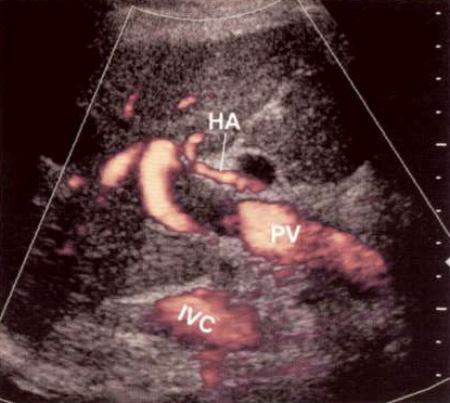

Ультразвуковые признаки тромбоза воротной вены на ранних стадиях характеризуются наличием гипоэхогенной области в зоне поражения сосуда. Тромбоз может быть полным или частичным, при этом могут расширяться воротная вена и ее притоки. Цветовая допплерография демонстрирует частичную или полную окклюзию. На спектральной допплерографии отмечается повышенная скорость кровотока в области прохождения сгустка при частичной обструкции (фото 6).

Фото 6. Сгусток крови в воротной вене. Усиленная допплерография демонстрирует неокклюзионный тромб в стволе воротной вены. НА – печеночная артерия; PV – воротная вена; IVC – нижняя полая вена